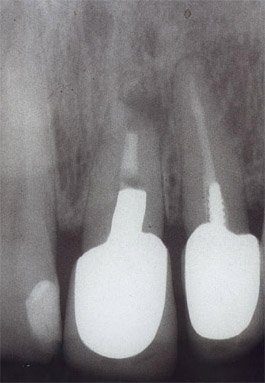

• Röntgenbilder

• Übersichtsröntgenbild